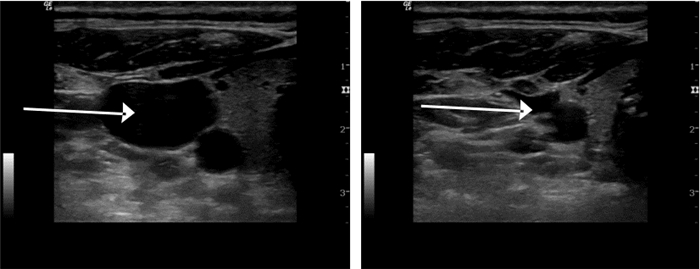

无论是动脉还是静脉在超声下都显示为圆形或椭圆形液性暗区,由于静脉血管缺乏富含弹性纤维的中膜,管壁较薄,相对于伴行的动脉更容易被压瘪,因此可以通过探头加压的方式来观察,首先被压瘪的是静脉(图 16)。打开超声的脉冲多普勒血流显像,可见动脉血流呈搏动样高频信号,而静脉血流呈连续性低频信号(如图 17)。

| 图 16 加压法辨别动静脉(左图为加压前;右图为加压后静脉压瘪) |